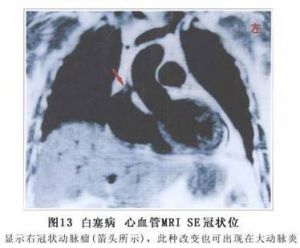

血管造影可發現腎動脈、腸系膜動脈、腦動脈等不同部位的血管呈節段性狹窄性改變(圖12,13,14,15)。